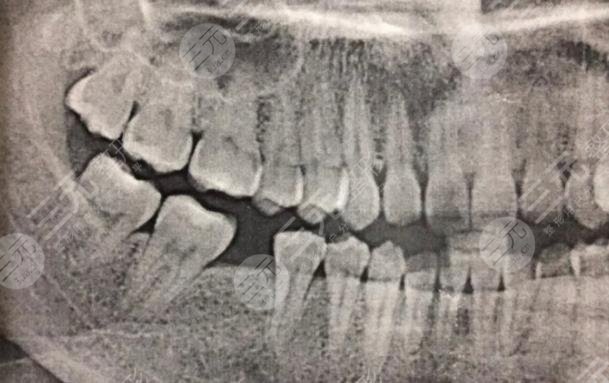

二、成都圣貝口腔醫(yī)院種植牙經(jīng)歷分享

我的牙齒有一顆牙齒壞了很久了,所以我一直想要修復,但是我又不想拔掉,所以就很糾結(jié),不知道怎么樣的方式才能夠改良,經(jīng)過朋友的一番介紹說,我還是選擇到口腔醫(yī)院里面檢查一番,然后再決定具體的緩解方法。在和口腔醫(yī)院的醫(yī)生溝通之后,他說像我這種方情況必須要把原有的壞牙拔掉之后換新的牙齒,不會有口腔造成疾病的情況。

成都圣貝口腔醫(yī)院種植牙經(jīng)歷分享

在聽了醫(yī)生的介紹之后,我決定選擇使用這種方法,沒想到這種方法確實GET了不錯的目的,現(xiàn)在我種植牙齒之后已經(jīng)有快兩年的時間了,沒有出現(xiàn)任何的副作用,平時也沒有出現(xiàn)牙齒疼痛的現(xiàn)象。